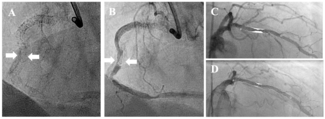

The authors report a case of early left atrial appendage occlusion (LAAO) device migration following the combined procedure of pulsed-field ablation and LAAO.